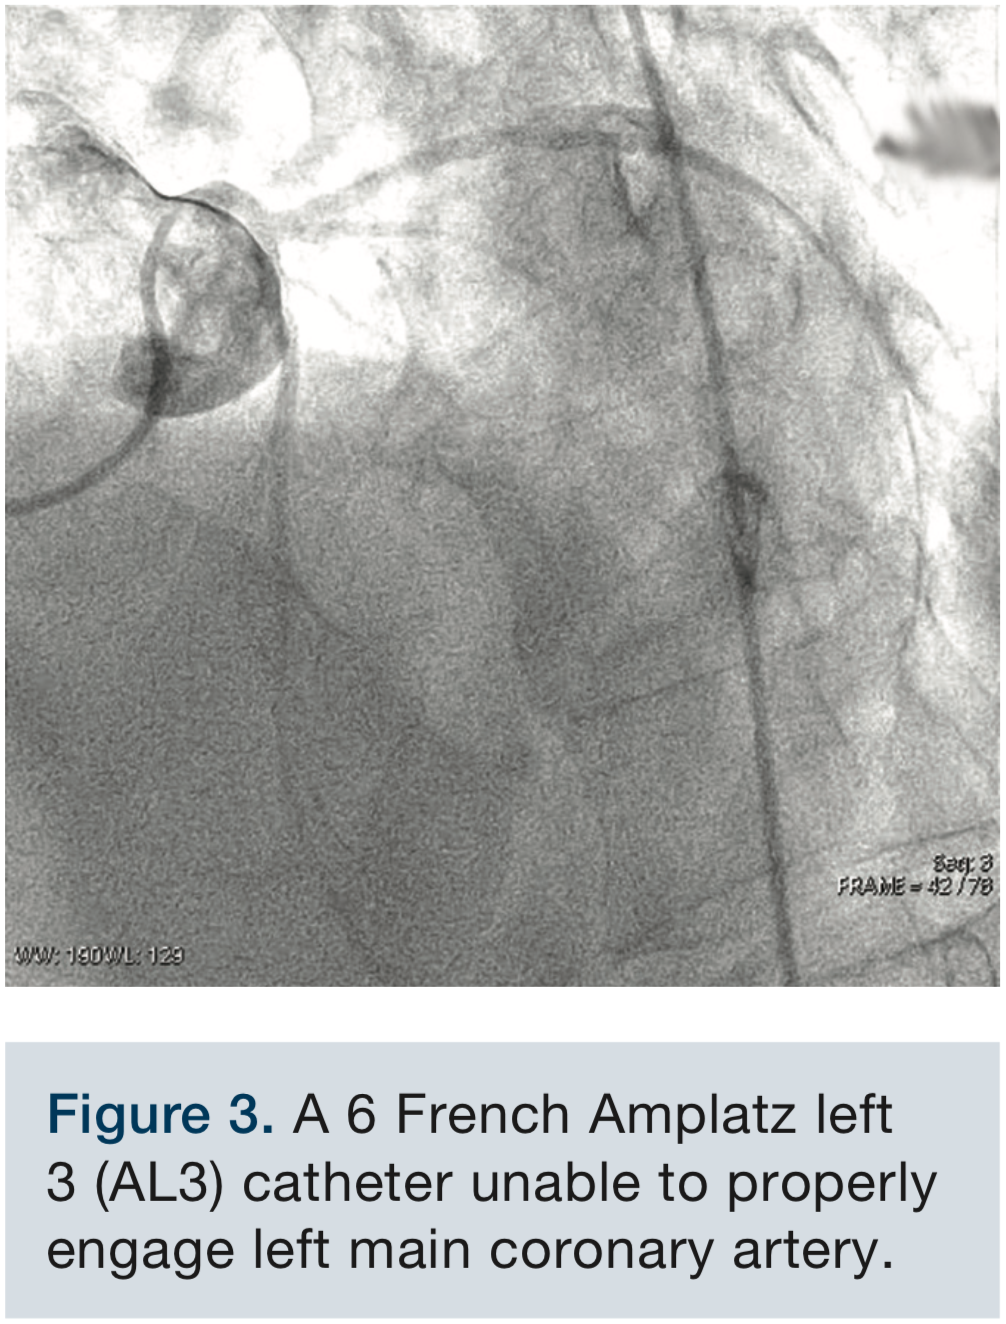

Multiple attempts to cannulate the left coronary ostium were unsuccessful, utilizing both a 6 French Judkins left 5 (JL5) (Figure 2, Video 1) diagnostic catheter and a 6 French Amplatz left 3 (AL3) diagnostic catheter. The AL3 was appropriately oriented with lack of length to reach the coronary ostium (Figure 3, Video 2).